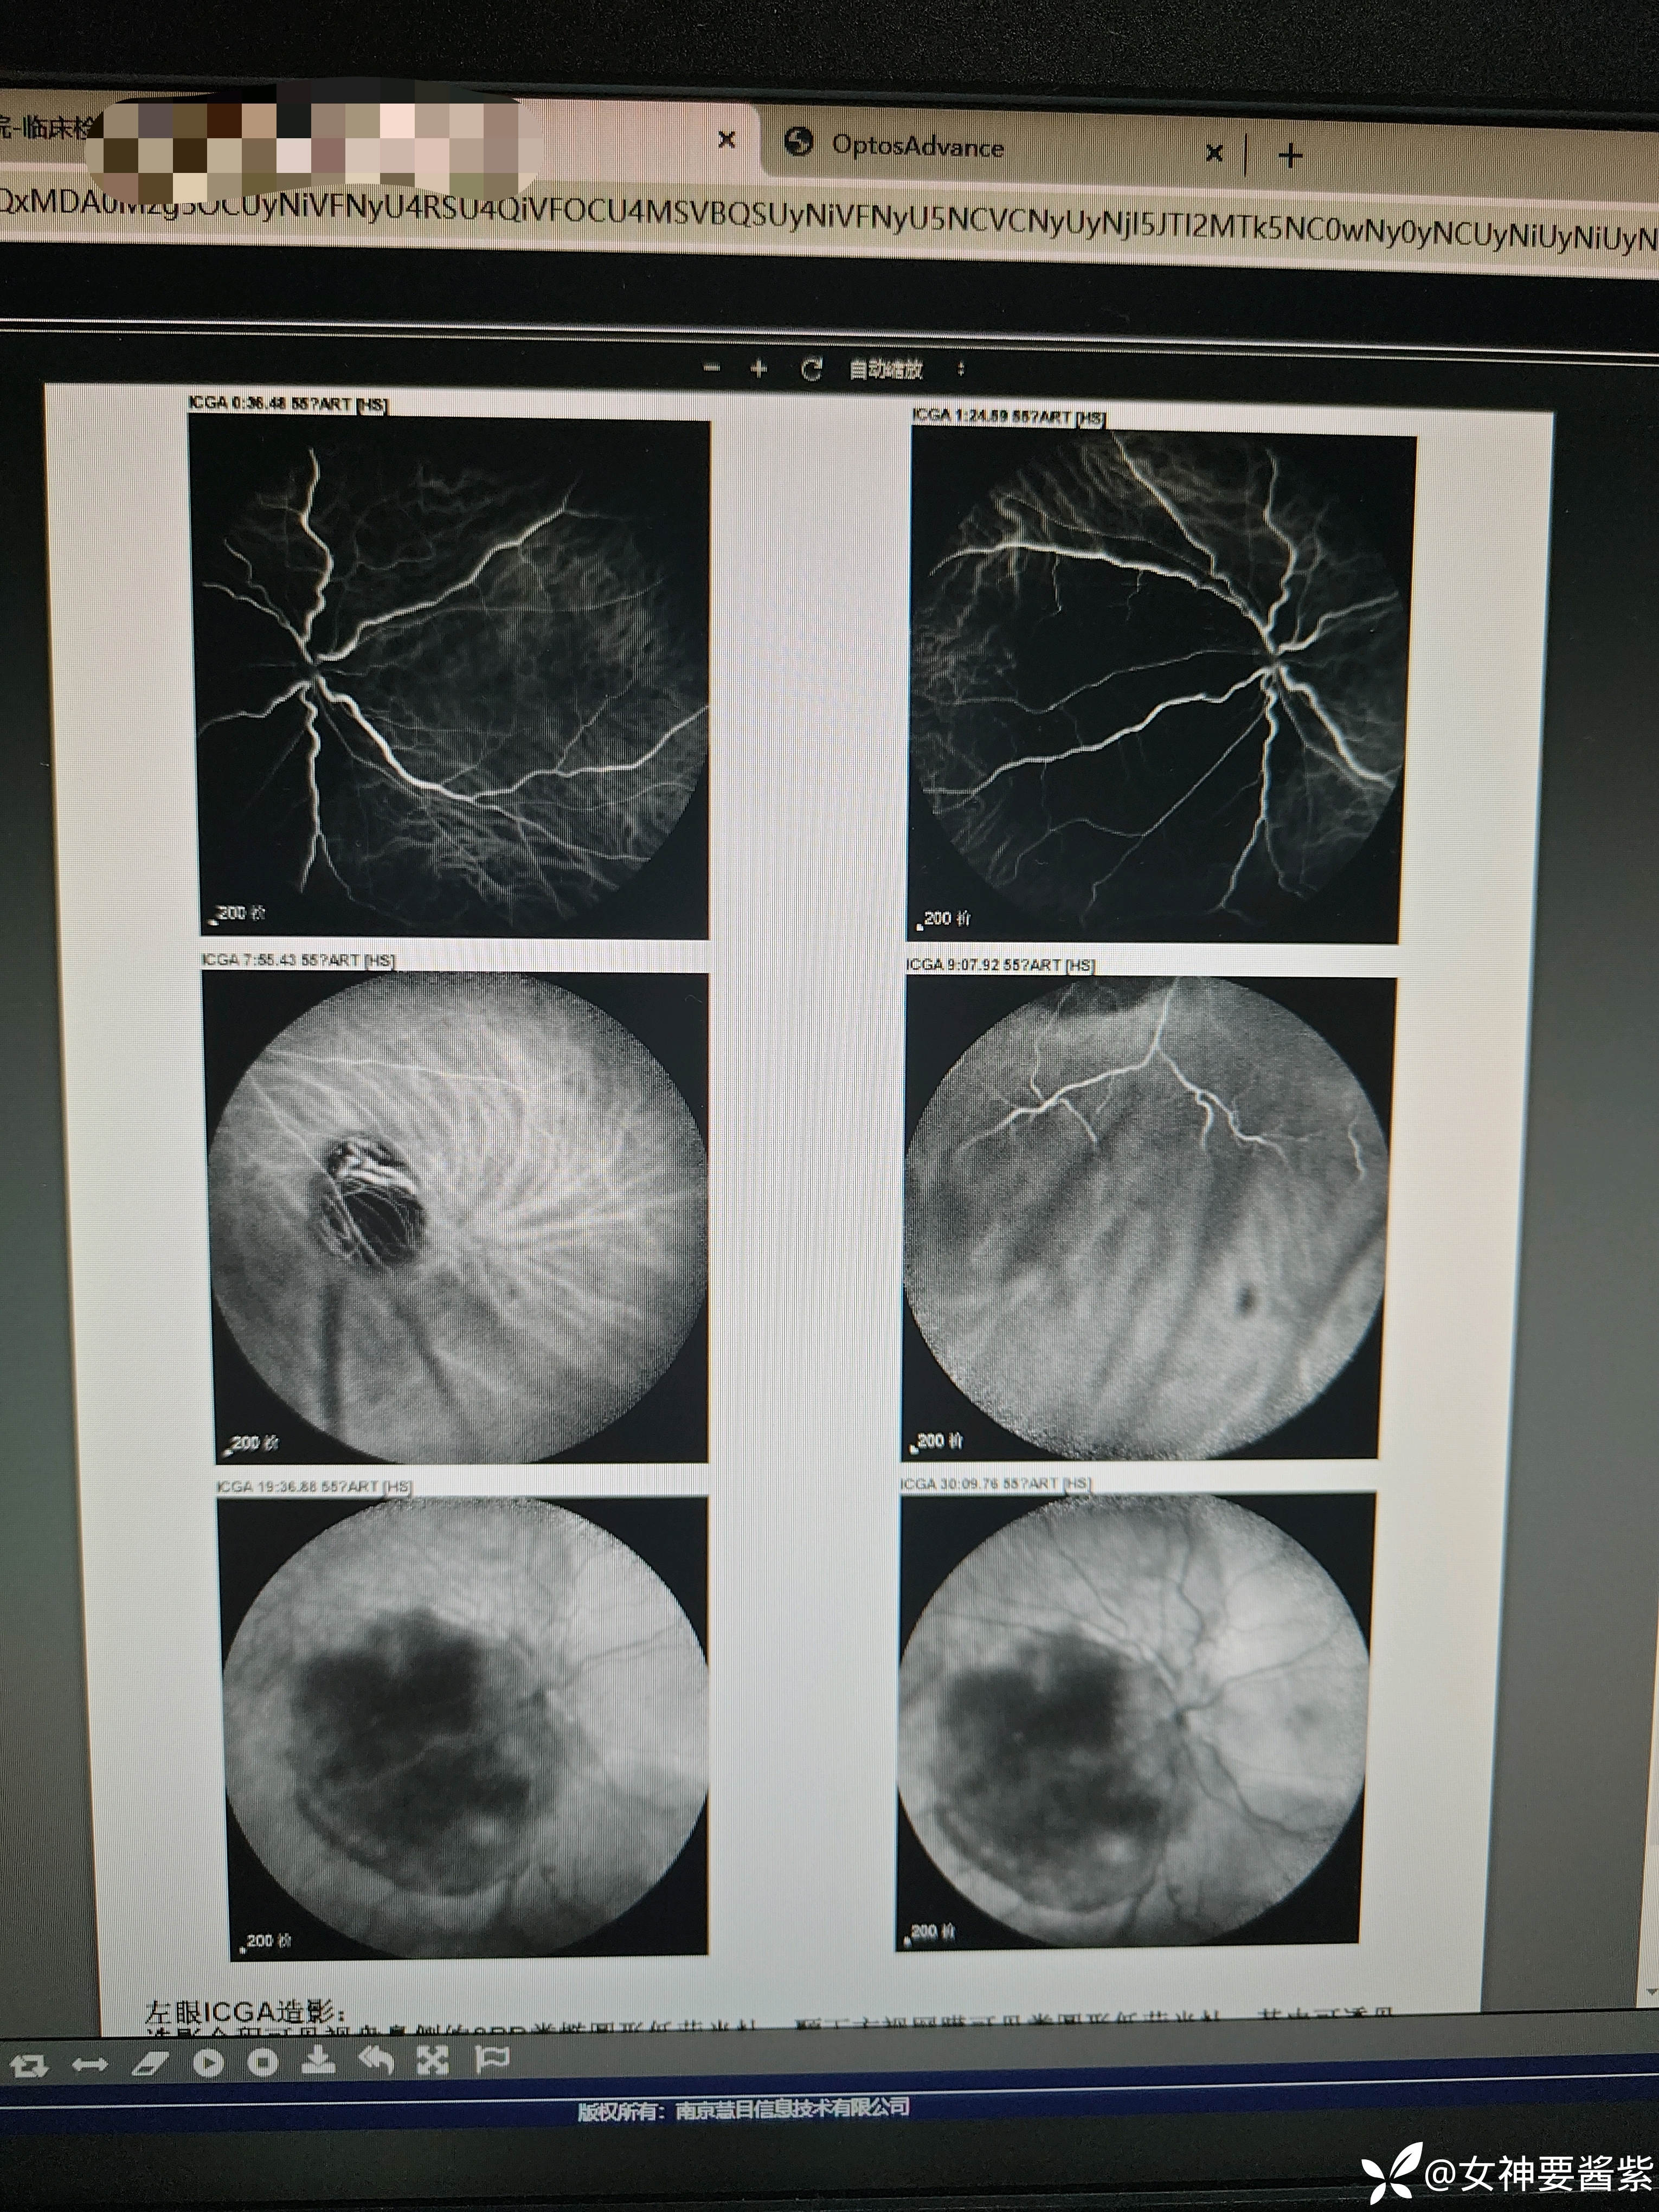

ICGA